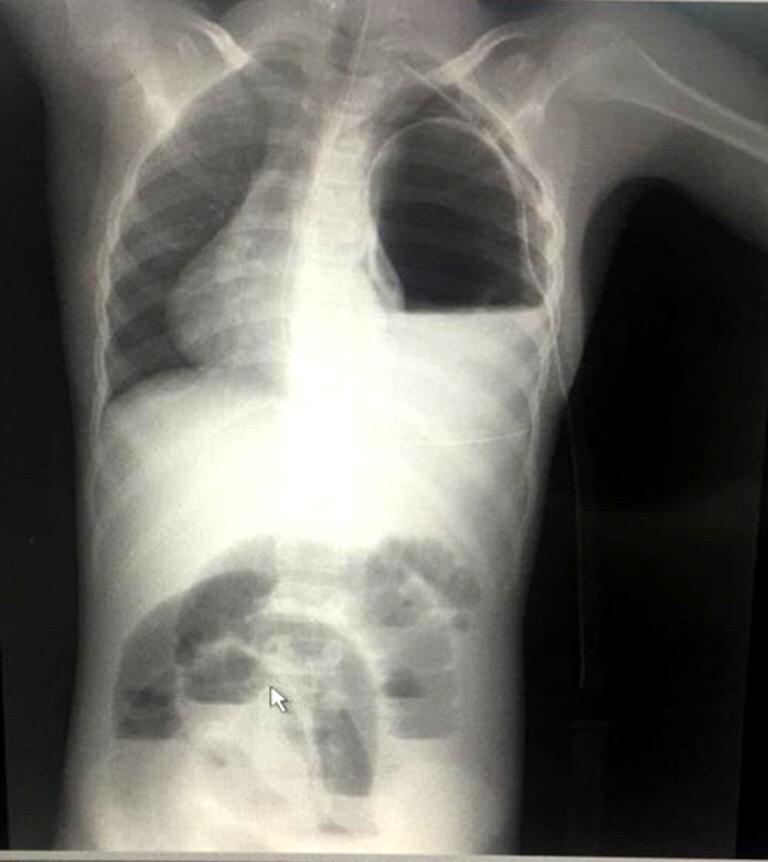

La hernia diafragmática postraumática puede aparecer tras un traumatismo del tórax y el abdomen contuso o penetrante. A causa de las lesiones coexistentes y la naturaleza silenciosa de la lesión diafragmática, el diagnóstico pasa en ocasiones desapercibido en fase aguda y puede manifestarse después, como un cuadro de obstrucción por los órganos encarcelados en el defecto diafragmático. En el adulto la hernia diafragmática traumática es una complicación conocida y poco común del trauma toraco- abdominal cerrado, que puede permanecer dormida por períodos prolongados y pasar inadvertido en un adulto mayor, haciendo que su diagnóstico diferido sea un verdadero reto para el médico. Además, puede manifestarse súbitamente, en el peor de los casos, con la muerte.

La doctora Robersy Pérez explicó el caso en cuestión “atendimos a un paciente de 9 años de edad, presentando dolor abdominal, tipo cólico, con 12 horas de evolución, insidioso generalizado, de leve a moderada intensidad, sin irradiación, con aumento de la medida que permite determinar la grasa acumulada en el cuerpo (perímetro abdominal) progresivo y vómitos, anteriormente en su etapa de recién nacido fue hospitalizado y tratado por meningitis, epilepsia controlada desde los 2 años de edad y con antecedentes de asma bronquial, siendo la última crisis a los 2 años”, detalló. Refirió que con el examen físico se encontró que sus condiciones clínicas del pequeño eran de cuidado: presentaba una moderada palidez cutánea y mucosa, deshidratación moderada, el abdomen estaba distendido y doloroso a la palpación de la zona abdominal. Detalló la doctora Robersy Pérez que en este paciente se encontraron con antecedentes quirúrgicos: extirpación del bazo (esplenectomía) más extracción del apéndice (apendicectomía) realizada en otro centro hospitalario y un trauma abdominal cerrado complicado, debido a arrollamiento vehicular hace años, donde se pasó desapercibido probablemente el defecto diafragmático “esto es raro encontrarlo en la edad pediátrica, pero a tener en cuenta en pacientes con accidentes de alto impacto”, dijo.